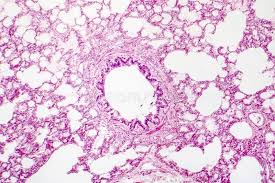

Histology (microscopic anatomy) refers to the study of animal tissues and how they form organs. Tissues that make up the lungs include bronchioles, epithelial cells, smooth muscle cells and alveoli, according to centre of the cell. The lungs tissues are made up mainly of squamous epithelial tissue (called alveolar epithelium in the lungs). Microscopic view of a histologic specimen of human lung tissue stained with hematoxylin and eosin. The study of human and animal tissues is known as histology or, in connection with disease, as histopathology.

Learn this topic now at kenhub! Epidermis (keratinised stratified squamous epithelium) origin: The lungs tissues are made up mainly of squamous epithelial tissue (called alveolar epithelium in the lungs). Struggling to differentiate between the alveoli and function: The lung is one of several organs that packs a large epithelial surface area into a compact volume. In thurlbeck, wm, churg, am, eds. Examples of normal cells and tissues are listed below with links to illustrative images. Your doctor will run a tube called an endoscope through. 2 mesothelium of serosa covering lung. Lung tissue is collected in a procedure called a lung biopsy, which can be done several ways: Microscopic view of a histologic specimen of human lung tissue stained with hematoxylin and eosin. Looking at lung tissue under a microscope is often the only way for a doctor to know which type of interstitial lung disease you have. Kuhn, c.normal anatomy and histology.